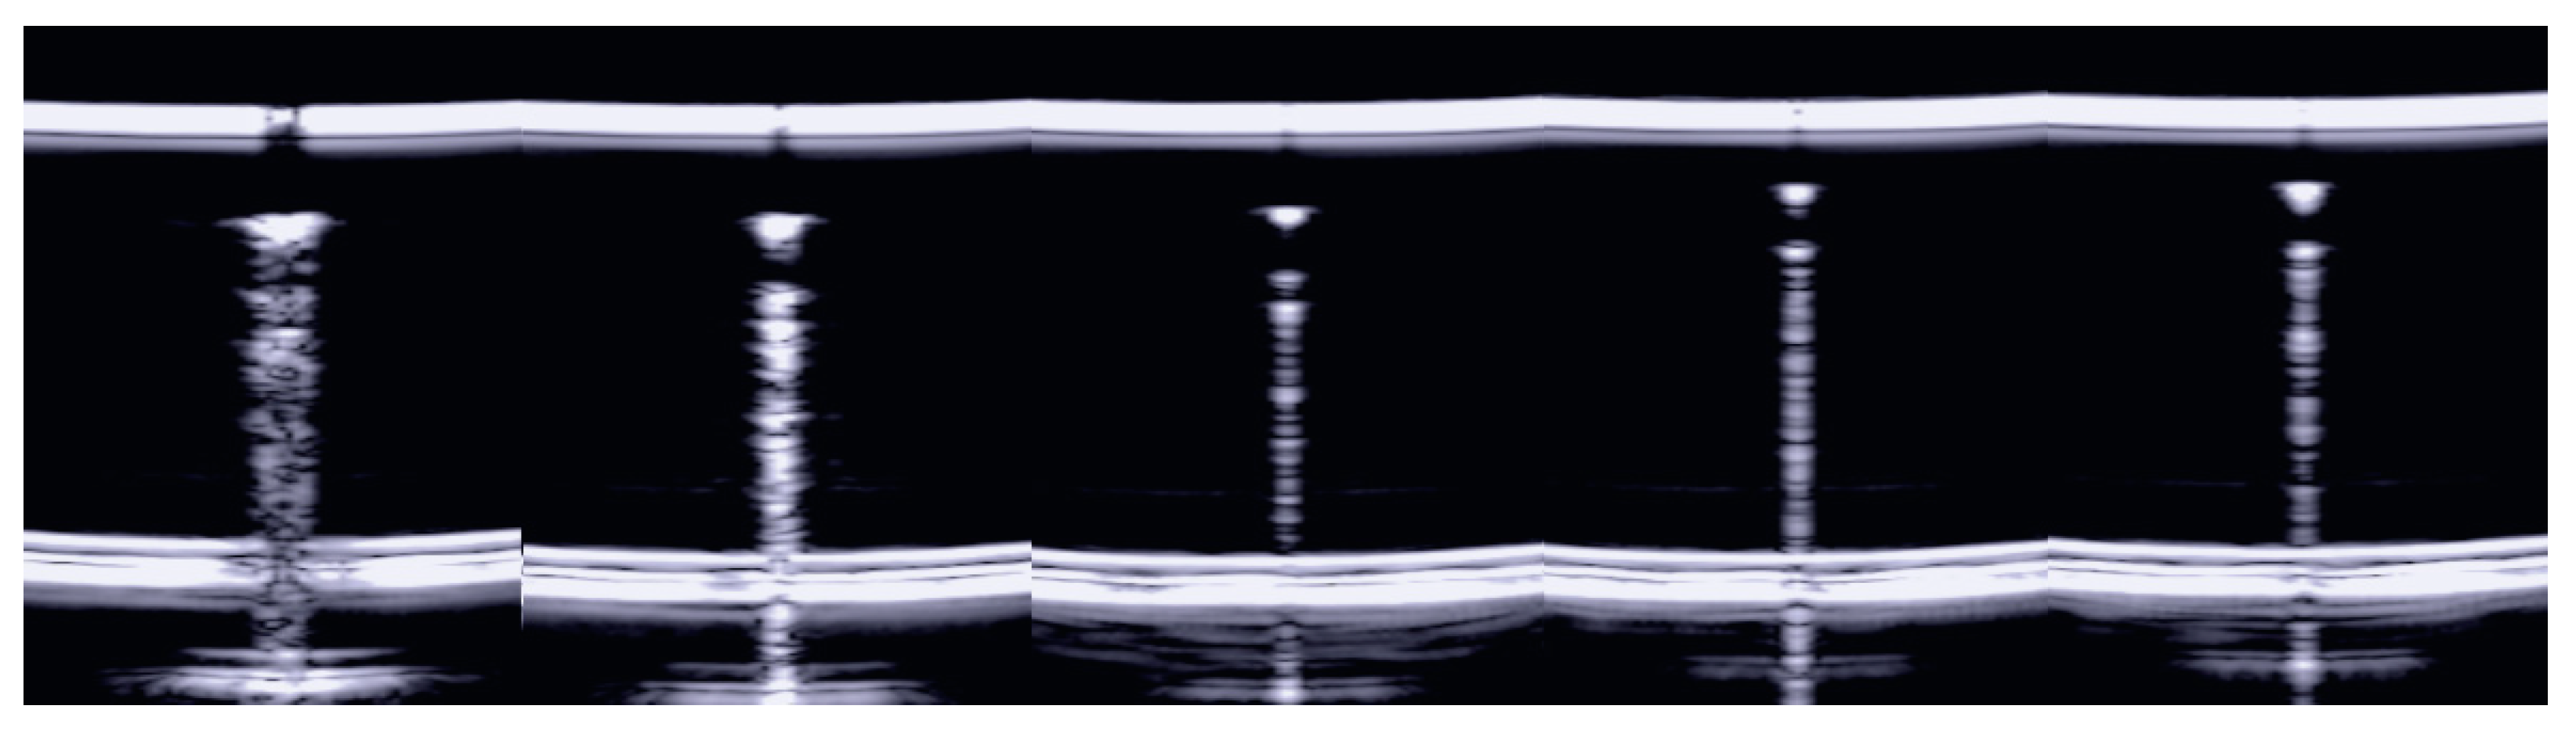

3.1. The Four-Step Method